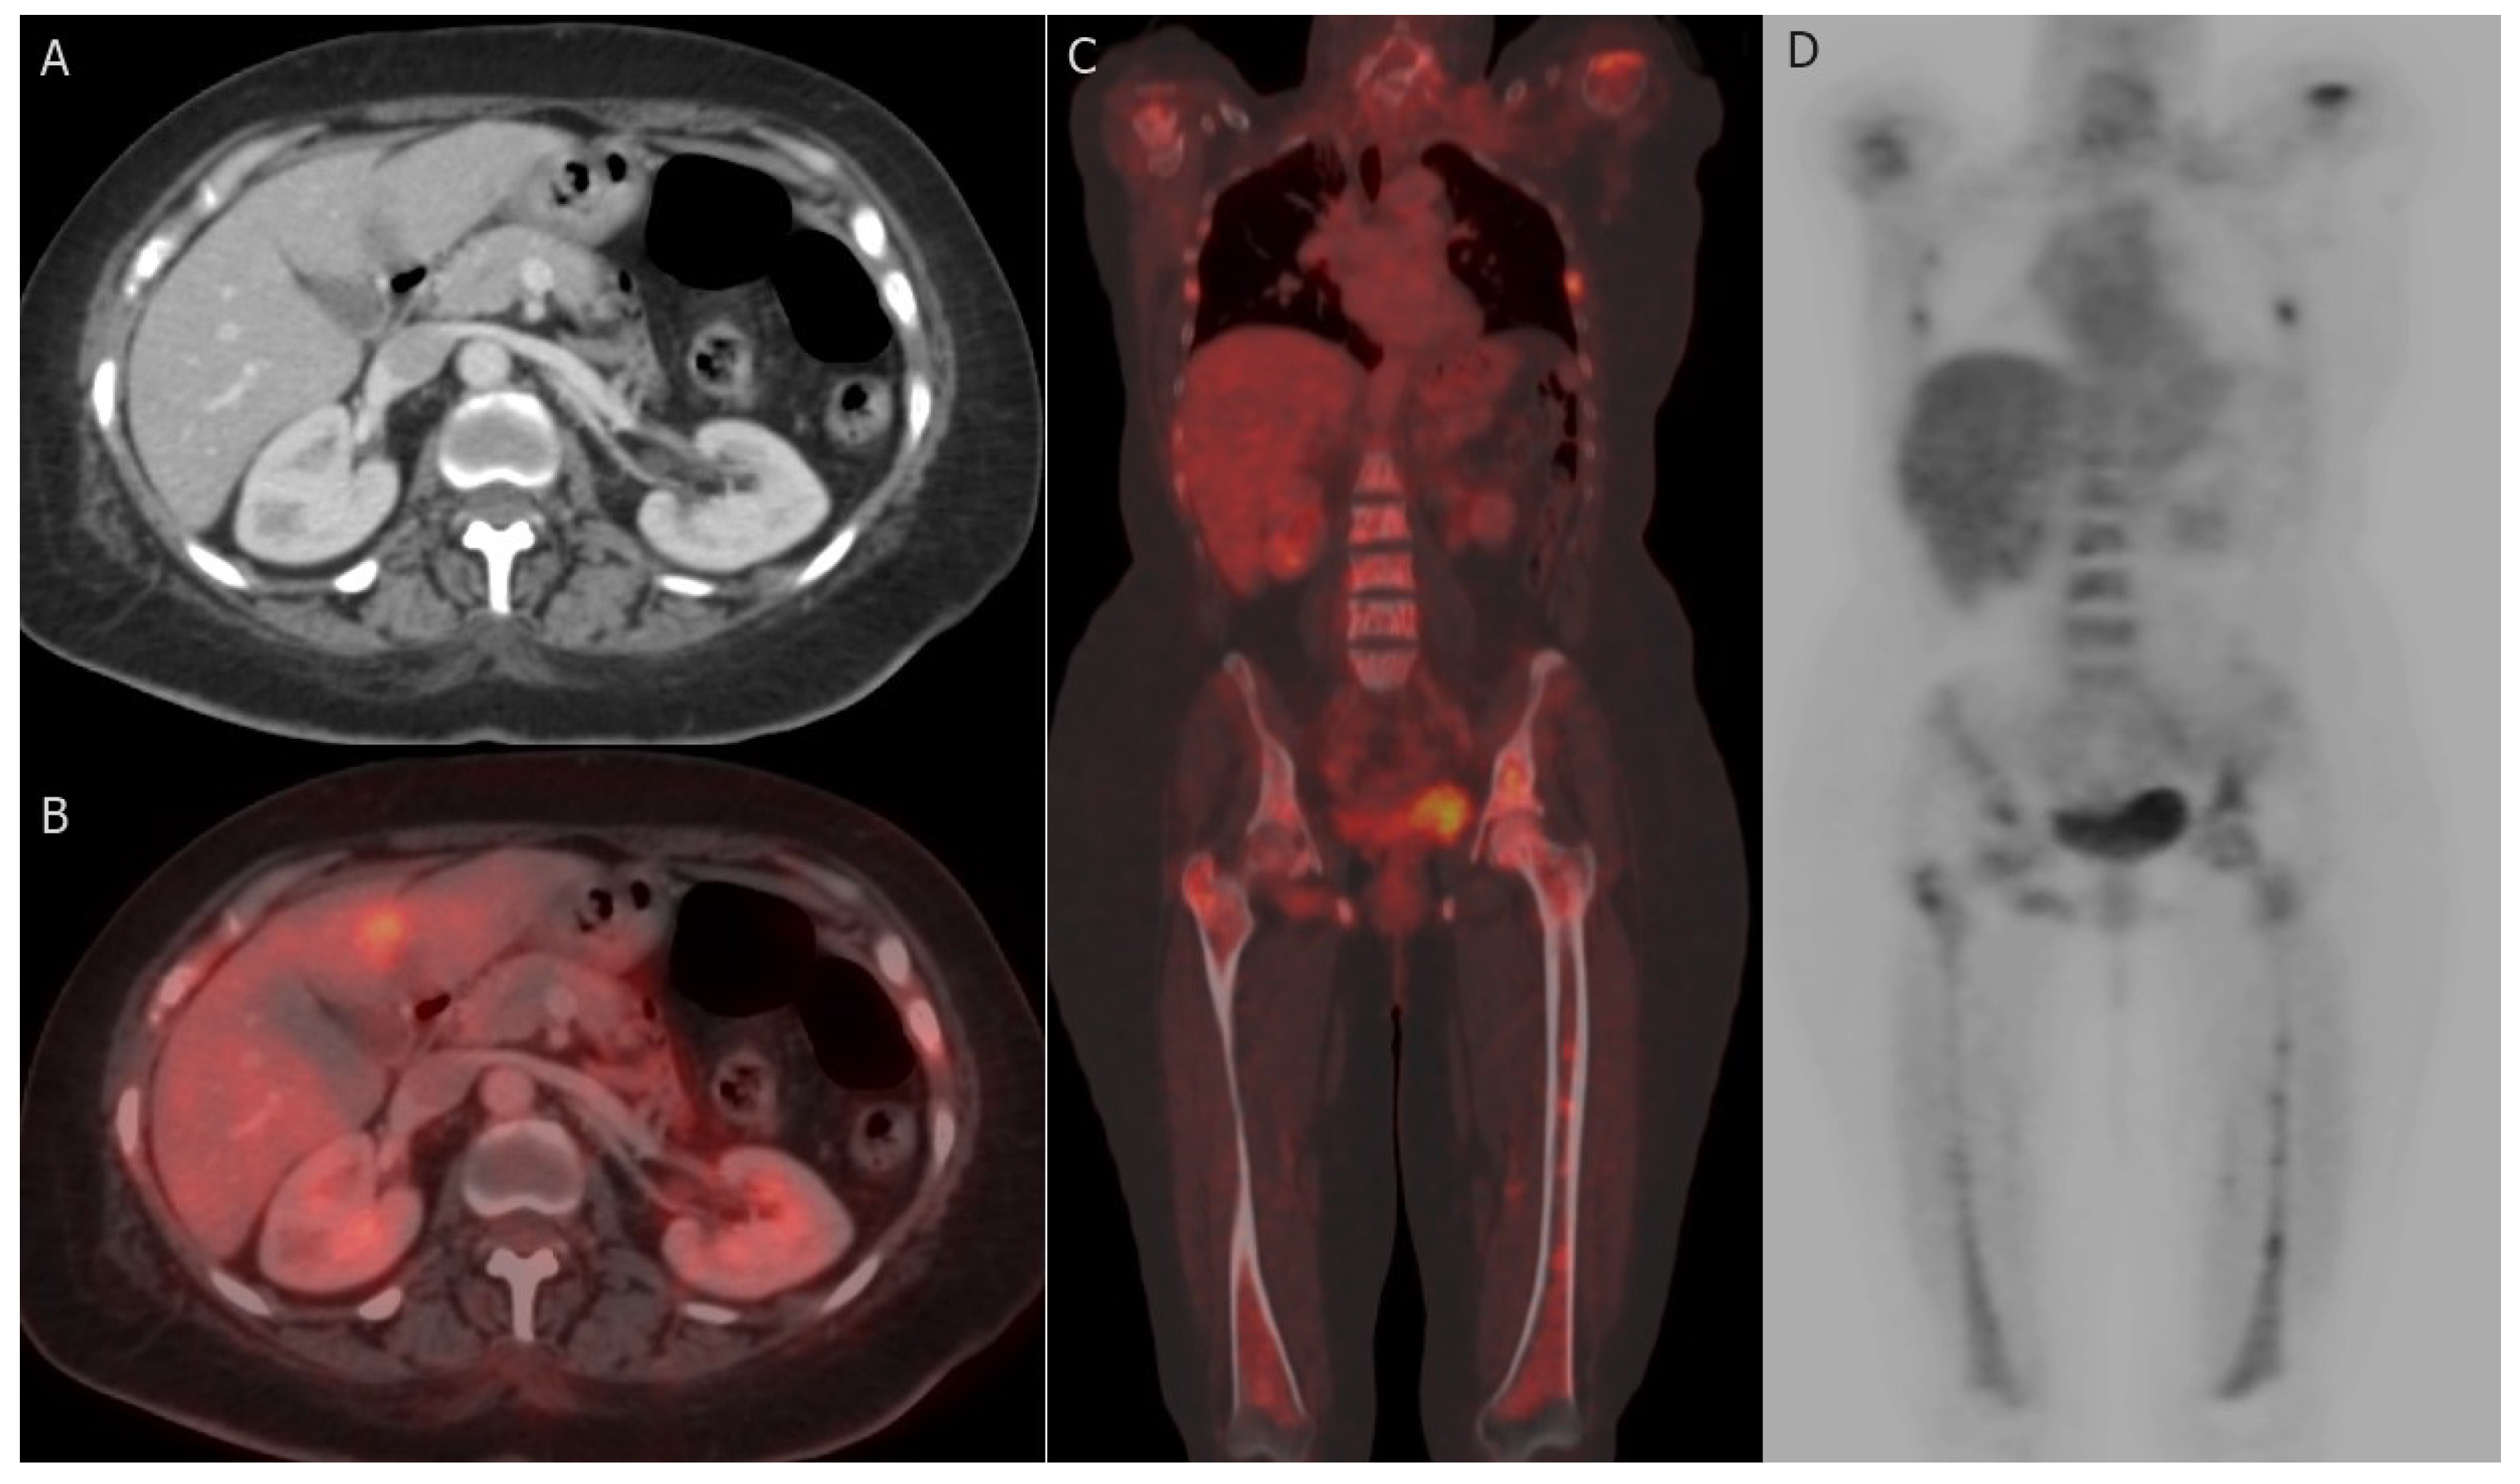

Figure 5.

Hepatic and bony metastases: 61-year-old woman with grade II invasive ductal carcinoma who underwent a right modified radical mastectomy. (A,B) axial post-contrast CT image and fused FDG PET/CT image reveal FDG-avid hepatic metastatic deposit at segment IV b with a maximum standardized uptake value (SUVmax) of 8.5. (C,D) coronal-fused FDG PET/CT and maximum intensity projection (MIP) images reveal FDG-avid multiple bony metastatic deposits at ribs, proximal humeri, lumbar vertebrae, iliac bones, and both femori with SUVmax of 9.8.